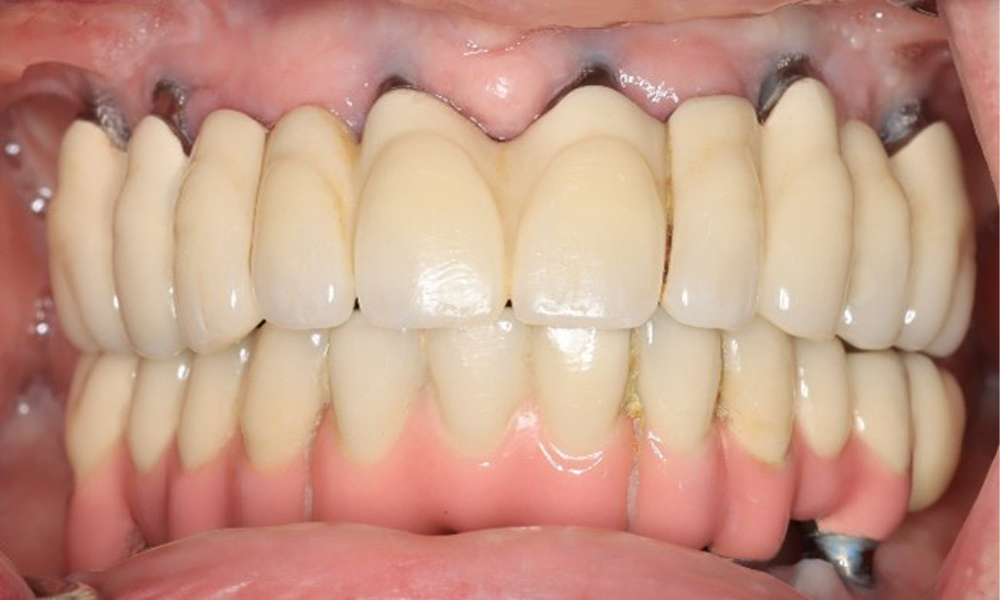

Frontansicht Gebiss (Ober- und Unterkiefer)

Abb. 3: Frontansicht